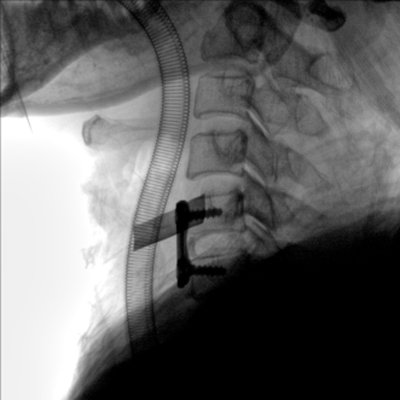

大尺寸動態(tài)平板探測器,高DQE、低噪聲、圖像清晰。采用多分辨率圖像增強(qiáng)處理技術(shù),不同部位不同圖像處理算法,滿足客戶多樣化的需求。

采用智能變頻脈沖透視技術(shù),優(yōu)化圖像質(zhì)量的同時降低輻射劑量,呵護(hù)醫(yī)患健康

圖形化操控界面設(shè)計:設(shè)有多種人體特征攝影參數(shù),操作簡便。雙向紅光十字定位系統(tǒng):實(shí)現(xiàn)無射線下的高效定位。信息共享:遵循DICOM3.0格式接口,可無縫對接云PACS系統(tǒng)。